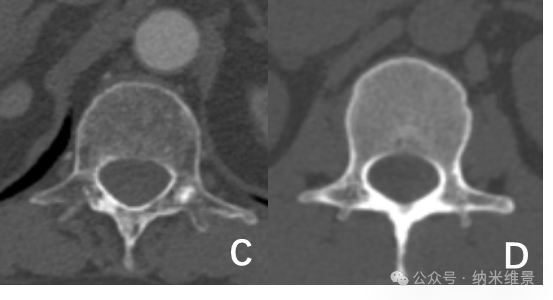

C. 老年骨质疏松患者螺旋CT图 D. 骨量正常的健康志愿者螺旋CT图

研究团队对100例受试者(老年组33例/中青年组67例)腰椎进行扫描,多项骨微结构指标变化显示:老年骨质疏松患者的骨小梁体积骨密度较中青年组显著下降,骨小梁连接密度有所减少。这种传统CT因分辨率不足难以清晰辨别的区域特异性差异,现可通过相控阵CT清晰呈现。

骨质疏松的隐匿性危害在于其"静默破坏"过程——骨小梁逐渐变细、断裂,骨骼内部结构变得酥脆,但传统检测手段常因分辨率不足难以清晰捕捉这些细微变化。

苏州大学附属第一医院与纳米维景的联合研究带来突破:相控阵CT凭借"光学旋转"技术,解决了传统CT依赖机械旋转导致的拖尾效应,将空间分辨率大幅提升,能够清晰地观测骨微结构,可精准识别骨质疏松早期的骨小梁改变,显著提高骨折风险预警准确性。